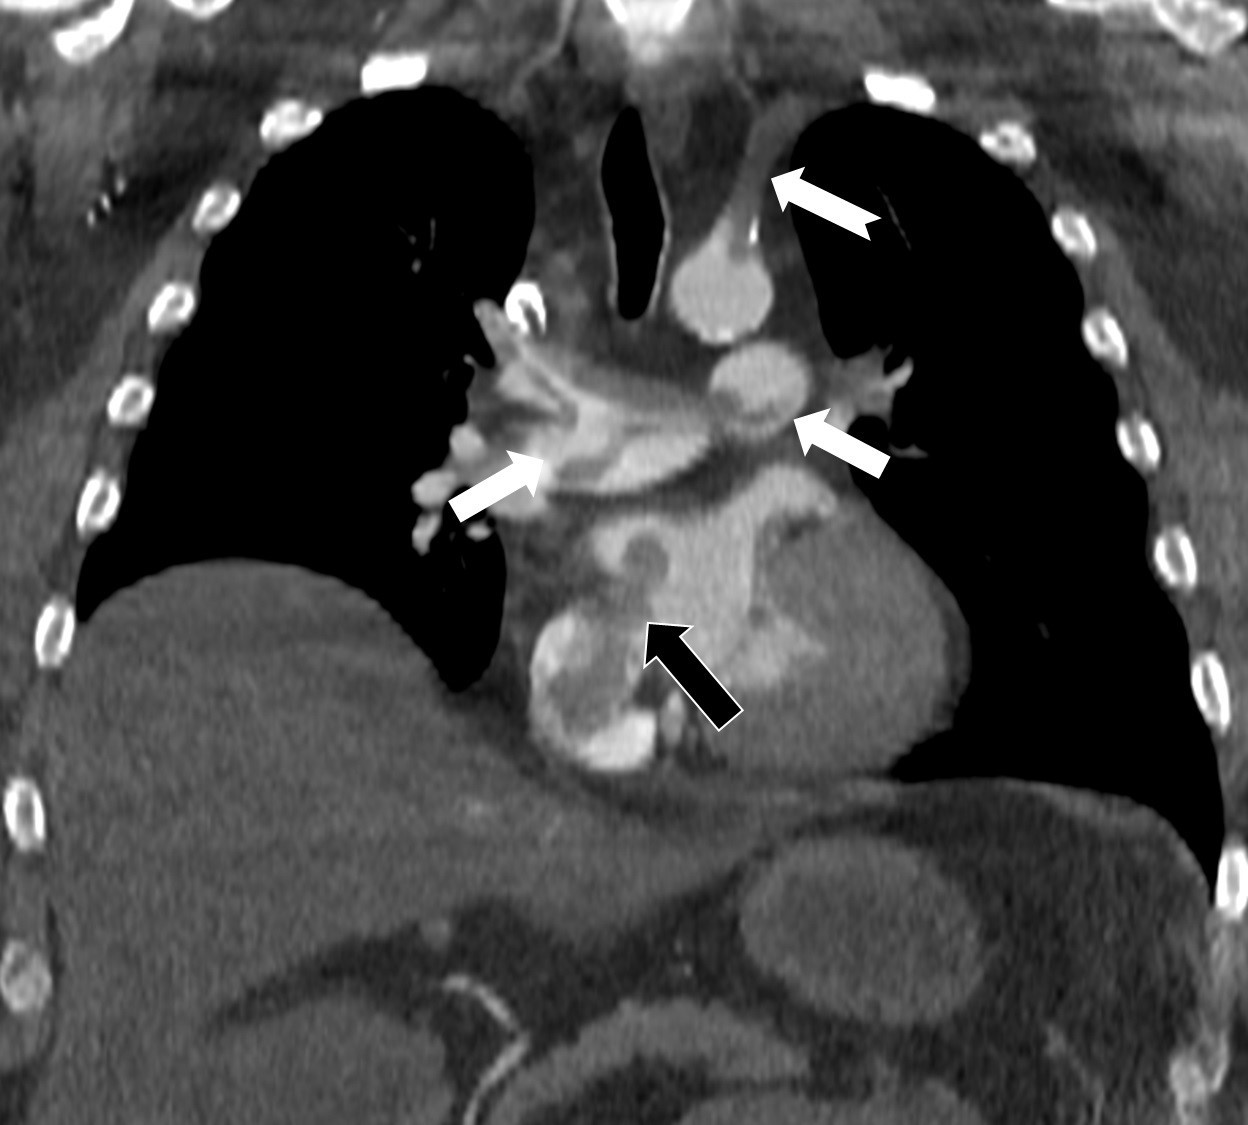

Kalp ve akciğer görüntülemesi alanındaki uluslararası bilimsel çalışmalarıyla tanınan Radyoloji Uzmanı Prof. Dr. Nevzat Karabulut, dünyanın önde gelen tıp dergilerinden Radiology dergisinin 2025 Kasım sayısında yayımlanan “Paradoxical Embolism with Clot-in-Transit in Atrial Septal Defect” adlı çalışmasında, penis ameliyatından 5 gün sonra ani göğüs ağrısı, nefes darlığı ve kol uyuşması şikâyetiyle hastaneye başvuran 60 yaşındaki bir hastada, daha önce fark edilmemiş kalp odacıkları arasındaki bir delikten geçen pıhtının hayati tehlike oluşturduğunu ortaya koydu.

Bir dönem Özel Denizli Tekden Hastanesi’nde de görev yapan Prof. Dr. Nevzat Karabulut’un yaptığı çalışmada; akciğerin bilgisayarlı tomografi anjiyografisi sayesinde toplar damarlardan kaynaklanan pıhtının akciğer damarlarını tıkaması yanında, kalpteki delik nedeniyle kalbin sağ tarafından sol tarafına geçerek ana atardamara ulaştığı ve sol kol damarını tıkadığı gösterildi.

Emboli görüntülemesi konusunda çok sayıda bilimsel çalışması bulunan Prof. Dr. Karabulut, genelde bacak damarlarından kaynaklanan pıhtıların ölümcül olabilen akciğer embolisine yol açması yanında, kalp deliği olan hastalarda ana atardamar yoluyla beyin, kol ve bacak gibi vücudun diğer bölgelerine de geçerek ani damar tıkanmasına (paradoks emboli) bağlı bulgulara yol açtığını belirtti. Prof. Dr. Karabulut’un çalışmasında nedeni bilinmeyen pıhtı atmalarında kalpteki gizli deliklerin mutlaka araştırılması gerektiği vurgulanarak ekokardiyografi ve bilgisayarlı tomografi tetkiklerinin erken ve doğru tanı koymada hayat kurtarıcı rolüne dikkat çekildi.